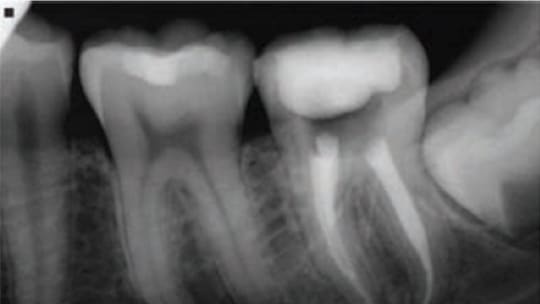

Return to "CE Sponsored by Zeiss: Restoring Endodontically Treated Teeth" zeiss-ce-fig2 Next Previous